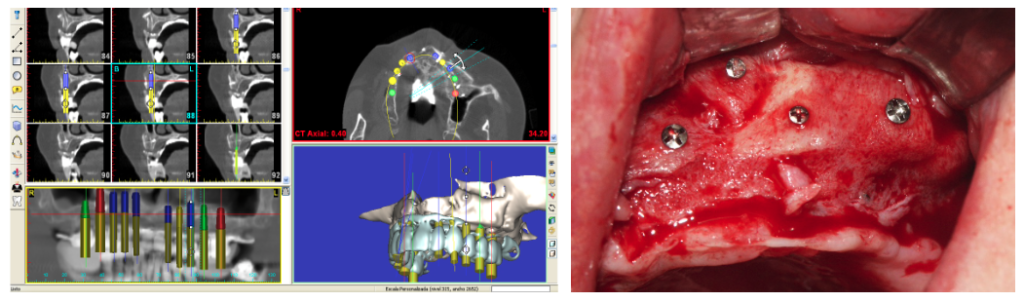

Injerto de cresta ilíaca (cadera)

Paciente con gran atrofia maxilar total (por edentulismo de muchos años de evolución).

Se realizó previa planificación informática con Symplant® Injerto onlay de hueso autólogo de cadera asociado a biomaterial y membranas de colágeno y elevación de seno bilateral . Conseguimos recuperar todo el proceso alveolar, para la posterior colocación de 8 implantes dentales y rehabilitación con prótesis fija metal cerámica.

Paciente con atrofia total del maxilar, resuelta con Implantes ZIGOMÁTICOS y 1 implante anterior. Planificación informática y Modelos 3D

Paciente con atrofia maxilar total, resuelta con la colocación de 4 implantes zigomáticos. . La prótesis definitiva ha sido realizada en metal-cerámica.

Planificación informática y modelos 3D

Atrofia maxilar total, resuelta con la colocación de 2 implantes zigomáticos y 2 implantes anteriores . Planificación informática y modelos 3D.

Foto de la planificación digital del caso